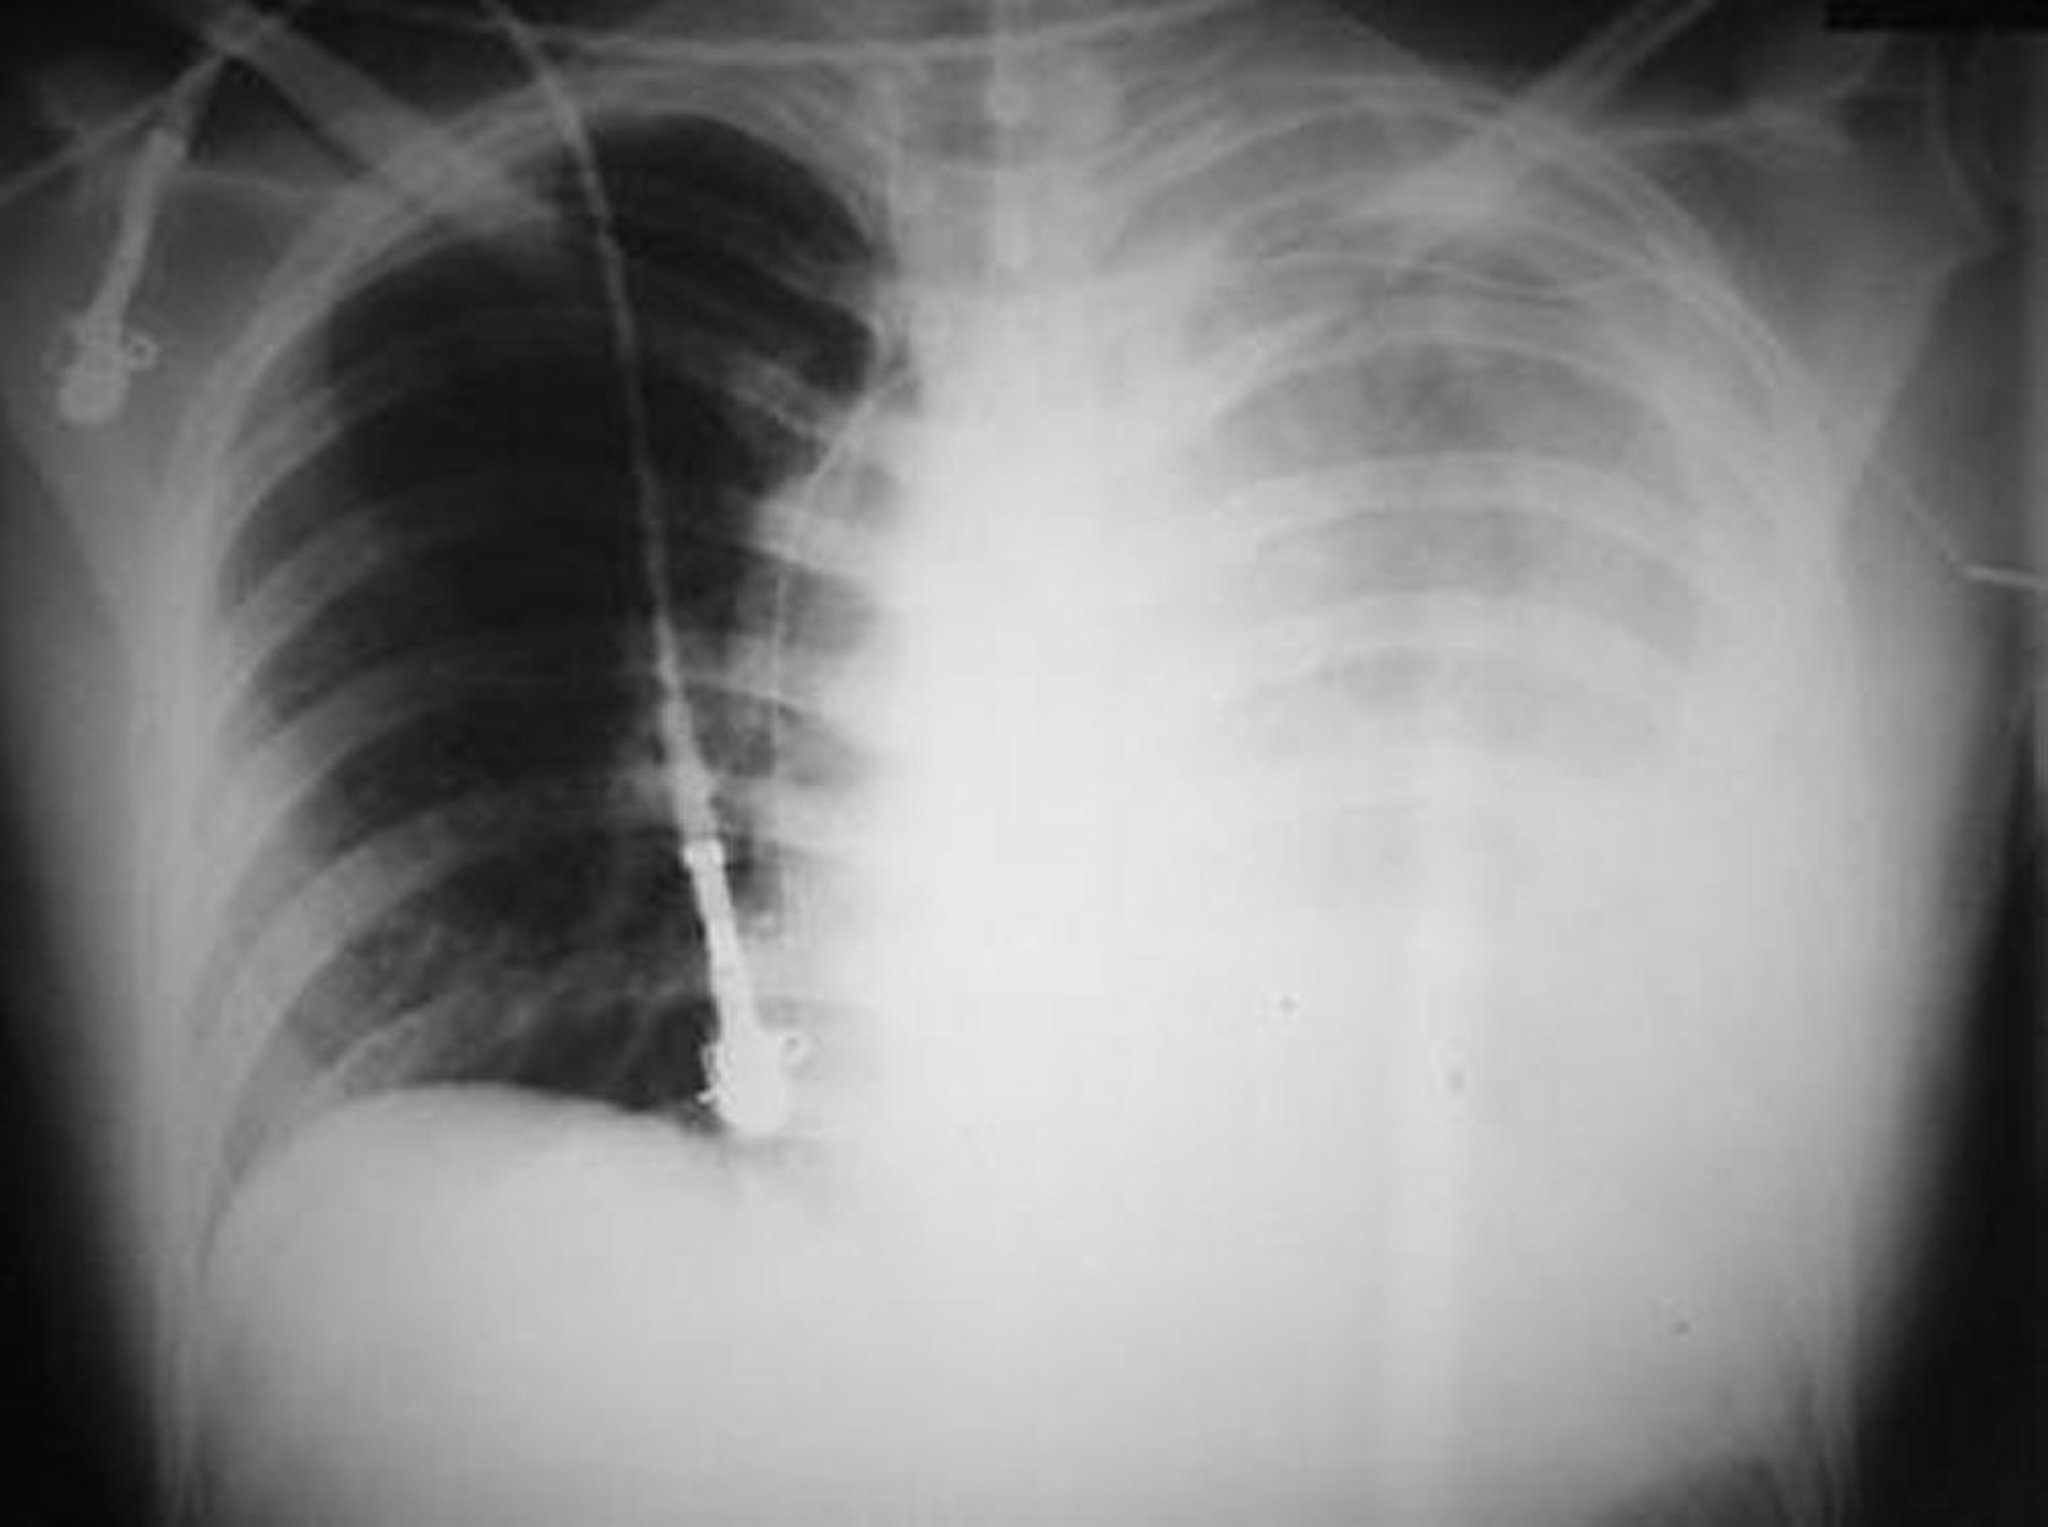

Esta fotografía muestra un hemotórax izquierdo masivo después de una herida de bala en el hemitórax izquierdo.